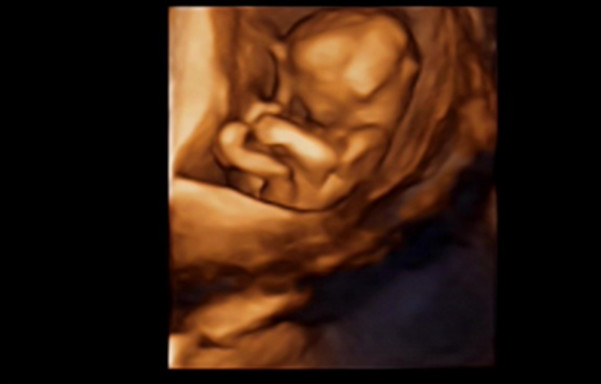

27岁的曹女士,已经怀孕六个月了。三天前,“孕味十足”的她,在丈夫的陪同下来到医院,准备进行提前预约好的四维彩超检查。但是万万没想到,检查结果让她的心情一下跌入低谷!通过影像显示,胎儿嘴唇中间竟然有一指宽的裂痕。经过医生再次仔细确认,腹中的胎儿确实患有唇腭裂,也就是“兔唇儿”。

唇腭裂患儿,是由于牙槽突间骨组织的缺失,造成上颌牙弓的完整性丧失,鼻基底部塌陷,牙槽突裂隙部恒尖牙萌出受阻。胎儿出生以后,需要通过牙槽突植骨术来完成唇部整形。手术具体怎么做,什么时候做,要做几次,这些都要根据孩子的具体病情。至于是否要生出来,这个就要由孕妇及家人自己决定。